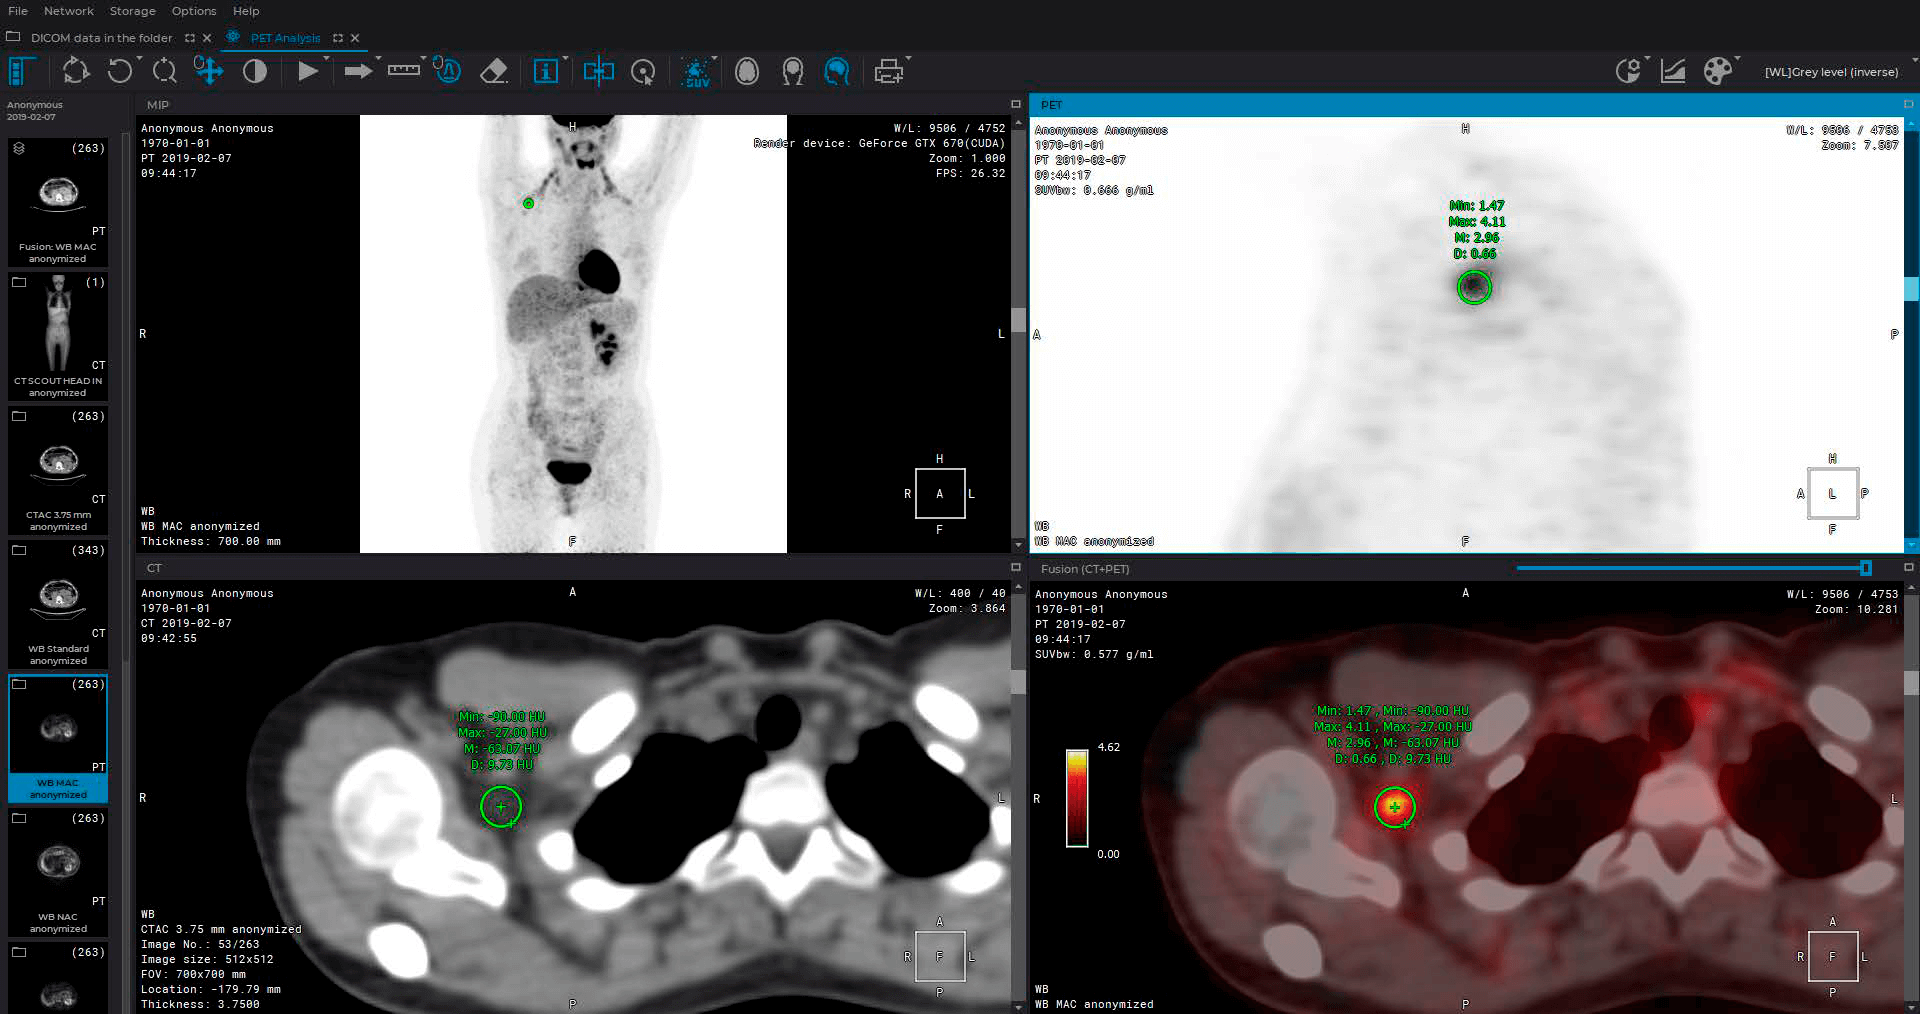

Advanced functionality

Advanced capabilities for working with 3D reconstructions

Advanced multiplanar reconstruction capabilities